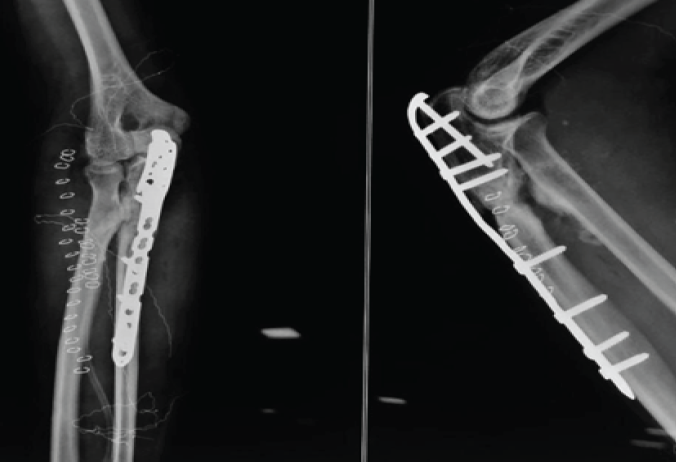

Immediate post-operative radiographs confirmed removal of synostotic bone and interposition placement (Fig. 6). At last radiographic follow-up, four patients demonstrated no re-ossification; one patient developed minimal, asymptomatic ossific recurrence abutting the graft but without functional limitation.

Figure 6: Immediate post-operative radiograph with removal of synostotic bone and interpositional placement.